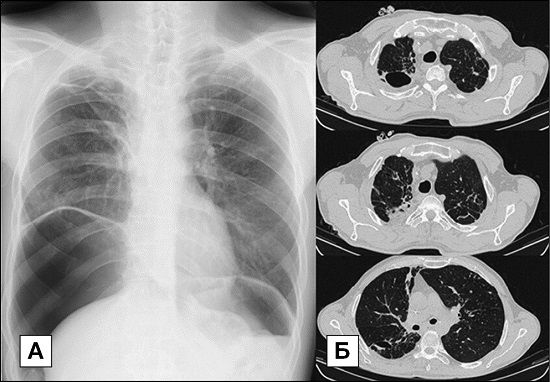

Фотографии и снимки КТ легких без контрастных веществ

Раздел: Визуальный дайджест